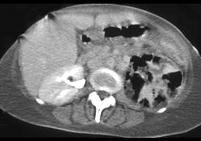

问题 女,63岁,高热、左侧腰痛伴尿频、尿痛,请根据所示图像,选择最可能诊断 ( )

选项 A、慢性肾盂肾炎 B、黄色肉芽肿性肾盂肾炎 C、化脓性肾盂肾炎 D、气肿性肾盂肾炎 E、左肾脓肿

答案 D